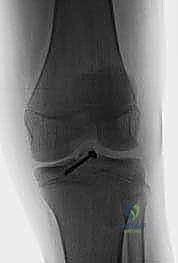

2. التصوير بالأشعة السينية (X-rays)

هي الخطوة الأولى والأساسية. يطلب الدكتور هطيف صوراً بأوضاع متعددة:

* صورة أمامية خلفية (AP): لرؤية الهيكل العام.

* صورة جانبية (Lateral): وهي الأهم لرؤية شوكة الظنبوب وتقييم درجة ارتفاعها وإزاحتها (لتحديد تصنيف مايرز ومكيفير).

| الحالات المستهدفة (التصنيف) | النوع الأول (Type I)، وبعض حالات النوع الثاني (Type II) التي يمكن ردها بنجاح. | النوع الثالث (Type III)، النوع الرابع (Type IV)، وحالات النوع الثاني التي تفشل في الرد المغلق. |

| آلية العلاج | شفط الدم من الركبة، ثم وضع الساق في جبس أسطواني (Cylinder Cast) أو دعامة صلبة في وضعية التمدد (أو انثناء طفيف 10-20 درجة). | إرجاع العظمة المكسورة لمكانها وتثبيتها ميكانيكياً باستخدام خيوط جراحية قوية أو مسامير طبية. |